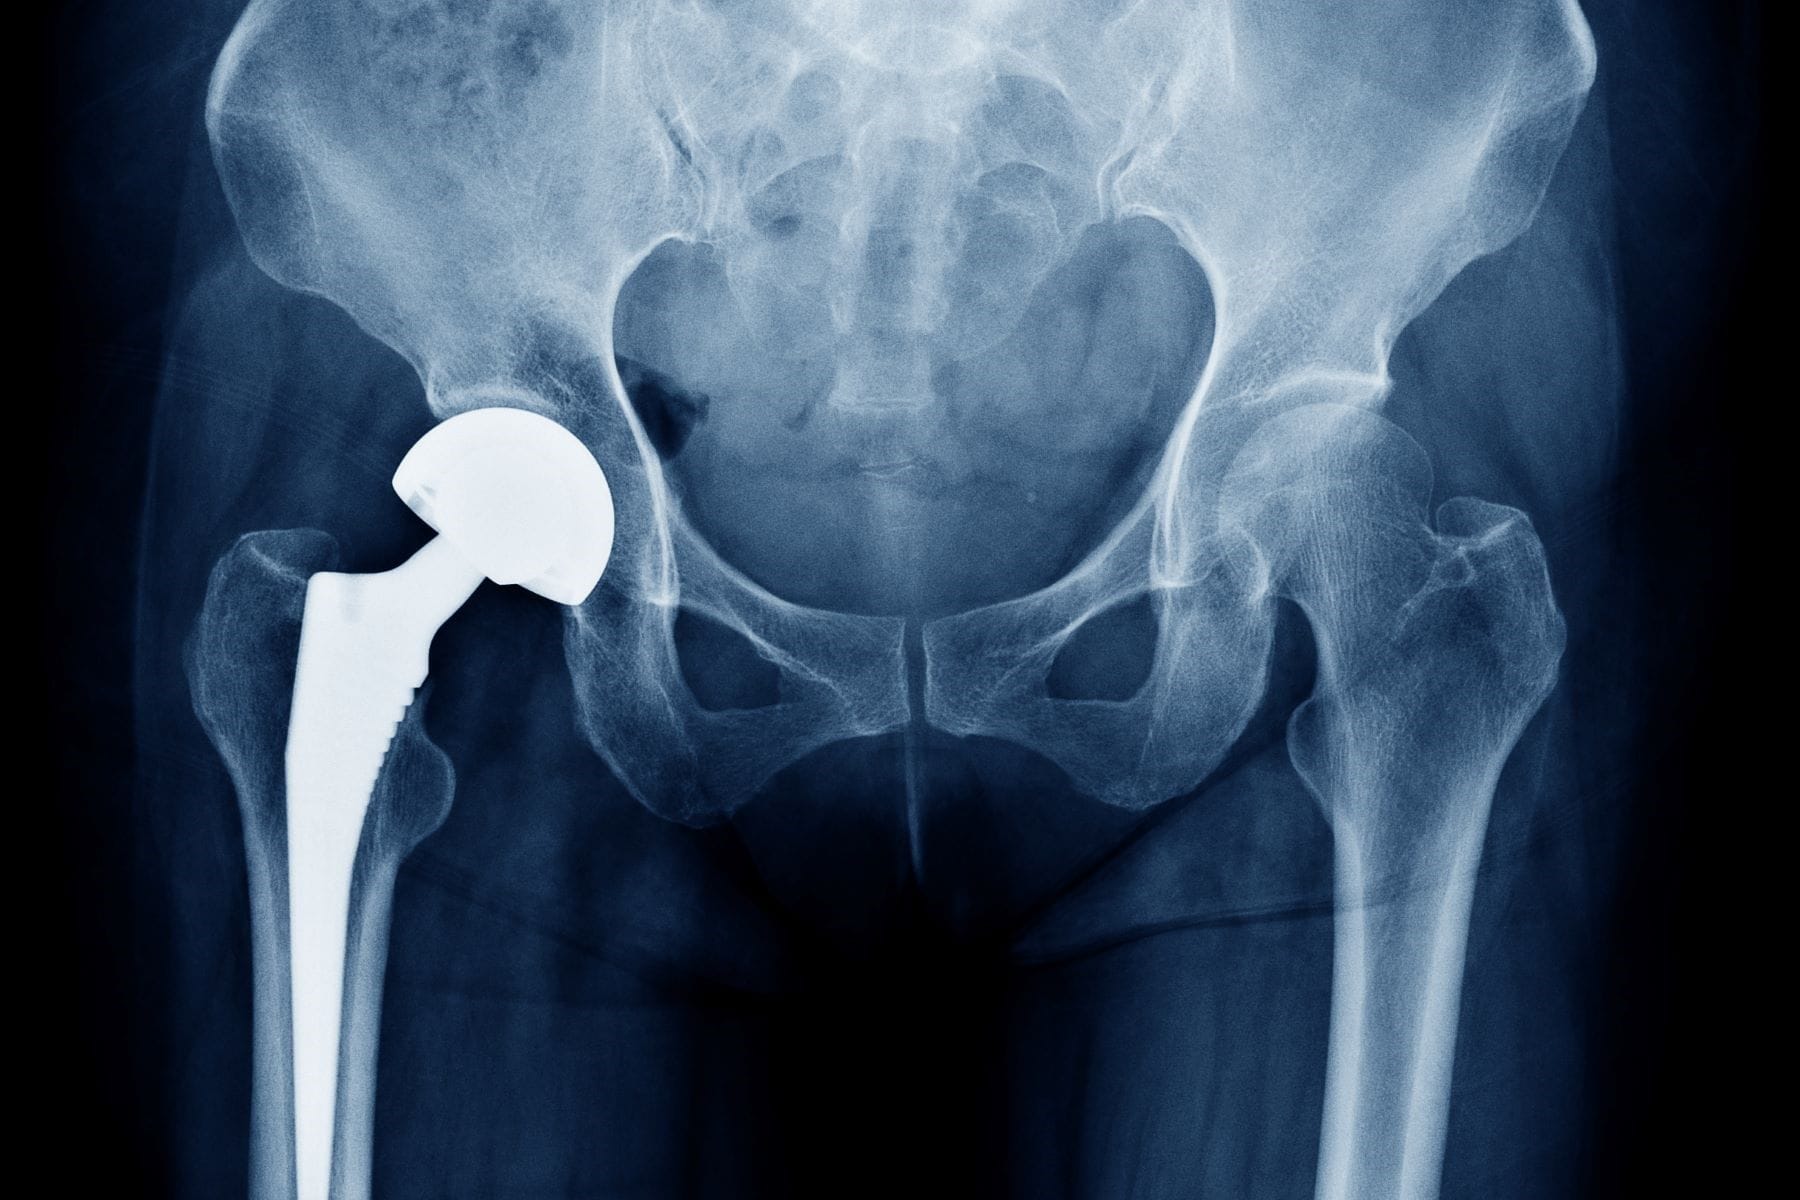

The issue at the heart of this high-stakes litigation were the injuries suffered by patients who received Johnson & Johnson’s DePuy Pinnacle metal-on-metal hip replacement devices. These implants, designed for patients who require total hip replacements, replace both the hip socket and the top of the thighbone. In devices like the Pinnacle system, these components are both made of metal. According to allegations made by the plaintiffs, these components can rub against each other and release metal debris inside the body. Thereby producing elevated levels of cobalt and chromium ions in the blood. In addition, the implants have also been linked to mechanical failures that compromise the structural integrity of the device. Numerous patients who have received Pinnacle’s devices have had to undergo revision surgery to remove the implant because of these complications.

Due to its allegedly high failure rate, plaintiffs have claimed to experience injuries such as implant loosening, extreme pain that sometimes spreads to the groin and back, difficulty standing or walking, metal poisoning of the blood, shedding of metallic debris inside the body, and intense soft tissue damage. Though Johnson & Johnson has not issued a recall for the DePuy Pinnacle hip implant, they did issue a global recall of a similar device in 2010 because of higher than expected failure rates. This device – the ASR hip implant – was also a metal-on-metal hip replacement device. In 2013, DePuy established a settlement program to resolve issues involving the ASR hip implants. Metal devices were originally designed to address the failures of older hip implant designs. Metal-on-metal devices were believed to be more durable than their predecessors.